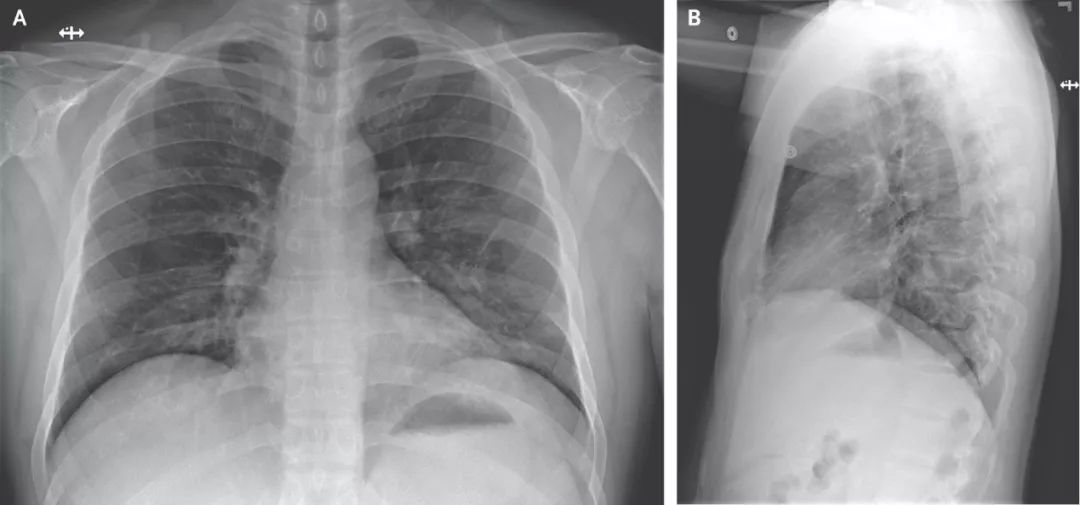

住院第五天,患者左肺下叶出现炎症迹象,并伴有呼吸困难症状。

图片来源:《新英格兰医学杂志》

住院第六天,患者开始持续高烧,呼吸也更加困难。